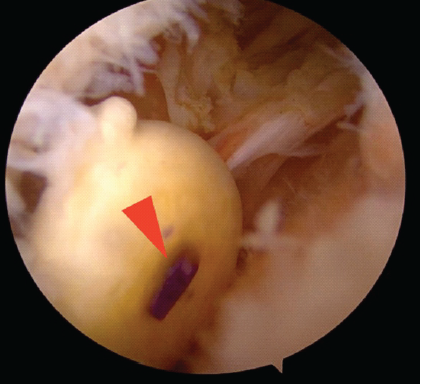

Diagnostic arthroscopy identified a mobile, whitish loose body measuring approximately 16 × 13 mm. A medial staple from the REGENETEN® implant was identified at the center of the specimen, encapsulated by surrounding tissue, while the rotator cuff repair site itself remained intact (Figs. 4 and 5). The loose body was excised arthroscopically.

Figure 4: Arthroscopic removal of loose body containing medial staple. Arthroscopic image of the excised loose body measuring approximately 16 × 13 mm, with the medial staple (arrowhead) of the REGENETEN® implant embedded at its center, surrounded by fibrinous tissue.